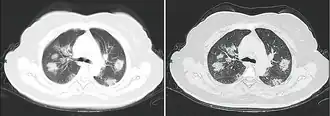

Tomografia computadorizada do tórax

Às vezes, tomografias computadorizadas (TC) do tórax podem ajudar a identificar e caracterizar o estado patológico pulmonar e produzir achados inespecíficos com a infecção por COVID-19. Um estudo descobriu que a sensibilidade da tomografia computadorizada para infecção por COVID-19 era de 98%, em comparação com a sensibilidade da RT-PCR de 71%. No entanto, o teste foi realizado em Wuhan, na China, e, por isso, pode não ser generalizado.[25][26] Grande parte dos achados consistia na presença de opacificação em vidro fosco na região subpleural e pavimentação em mosaico. Esses achados são inespecíficos, pois também são encontrados em outros tipos de pneumonia. Nenhum estudo avaliou, ainda, a precisão e o valor discriminatório das tomografias para distinguir a COVID de outras pneumonias virais.[27][28]